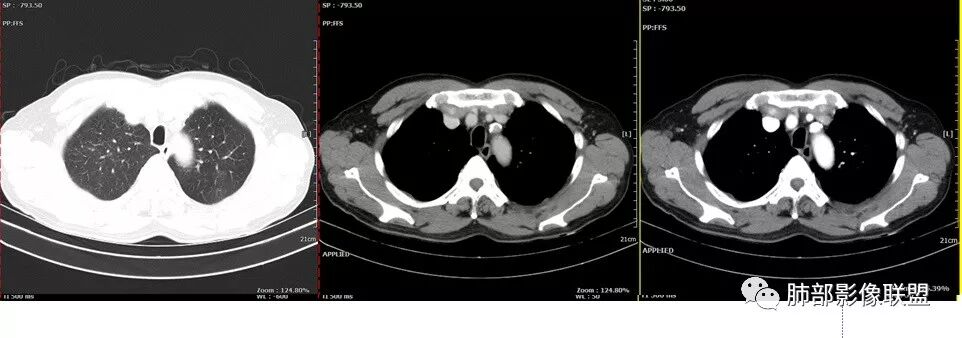

胸CT:左肺上叶前段实变,其周围及左肺上叶尖后段可见肺气肿背景下渗出性病变,病灶内可见支气管扩张,气道壁呈不规则增厚,双肺散在小结节状影;右肺下叶结节影,内可见空泡,边缘模糊,不规则。增强可见病灶内血管造影征,右肺门增大,纵隔淋巴结多发肿大。

患者中老年男性,发热,咳嗽5天,胸痛2天。慢性咳嗽,咳痰10余年,目前出现活动后胸闷气短,有基础糖尿病、高血压病史,查白细胞正常,CRP增高,IGE增高,CEA轻度增高。胸部CT:左肺上叶片状密度增高影,边界清楚,内血管穿行,呈蜂窝网格状,内有磨玻璃影,部分支气管壁增厚,部分有扩张,部分有近段粗细不均;右肺下叶可见一结节影,有凹陷,有膨隆,似有结节感,右侧肺门淋巴结肿大,纵隔多发淋巴结肿大、部分伴有钙化。综合考虑恶性病变,左上肺粘液腺癌可能,右下肺小细胞癌?两源论考虑:左上肺粘液腺癌或粘膜相关性淋巴瘤?右下肺结核球伴肺门淋巴结肿。

左肺上叶病灶长轴与支气管走形一致,提示沿支气管分布病变,倾向于炎性,大家可能怀疑这个病例是来源于胸膜下为主的,胸膜下来源首先整体是来源于胸膜下,与胸膜下之间没有间隙,而这例与胸膜下有间隙。而且这个病变是沿支气管朝外蔓延的,而胸膜下来源的是朝内蔓延的,唯一给我们错觉的是靠近纵隔胸膜这个地方有问题。但是靠近纵隔胸膜这个位置实变不是靠近胸膜实变,它边缘收缩的,没有膨隆的迹象。我们看到里面支气管直达远端稍扩张,是以中央间质为主、小叶间隔朝外蔓延,有间质也有实质病变,走向是沿中央间质方向走的,我个人倾向炎性病变。    问题是右下叶病灶怎么解释?右隔上、右肺门各有一个结节。这个病人有急性咳嗽、胸痛的病史,还有糖尿病病史,周围渗出比较明显,应该警惕炎性病变,要警惕克雷伯杆菌、结核、金葡菌霉菌,因为糖尿病人经常好发这些病菌感染。那么右下叶病变怎么考虑?能不能一元论?    左肺病灶是一个急性渗出为主的病变,一个急性感染的迹象;右肺下叶背段结节,没有看到支气管,增强图支气管壁增厚,局部小结节,呈分叶状,支气管堵塞,没有粘液栓样指套样改变,但是里面有强化,我倾向于癌,其次待排结核。我还是倾向于癌的可能性,恶性可能性大一些,可惜我看不到支气管腔内。还考虑有没有淀粉样变性的问题,弥漫钙化灶最常见的一个是结核,另一个是淀粉样变性。叶段支气管壁有弥漫增厚的迹象。所以淀粉样变性跟结核都要考虑。

2.左肺上叶大范围高密度影,几乎占据整个肺叶,没有体积改变,尽管小叶间隔显示明显,但初诊还是首先会想到社区肺炎,尤其是结合患者有发热及左侧胸痛的临床表现。